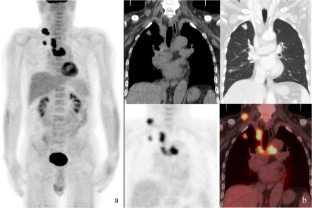

This study aimed to investigate the multiple values of 18F-FDG PET/CT in detecting malignant tumors, evaluating myopathy, and determining interstitial lung disease in patients with idiopathic inflammatory myopathy (IIM). We retrospectively analyzed the data of 38 patients who were examined by 18F-FDG PET/CT and eventually diagnosed as IIM. We also collected the data of another 22 cases with negative PET/CT as the control. Pulmonary HRCT images were acquired simultaneously with regular 18F-FDG PET/CT imaging for each patient. Image analysis included the presence of malignant lesions, muscular FDG uptake, and interstitial lung disease and its imaging features. IIM was classified into polymyositis (PM), classic dermatomyositis (CDM), and clinical amyopathic dermatomyositis (CADM). All suspected malignant lesions were confirmed by histopathological examination. Interstitial lung disease was diagnosed by HRCT. Rapidly progressive interstitial lung disease (RP-ILD) was determined according to clinical follow-ups. The significance of 18F-FDG PET/CT in the detection of malignancy, observation of activity of myopathy, and determination of interstitial lung disease in IIM patients was explored based on the final clinical diagnosis. In the 38 patients with IIM, 3 cases were classified as PM, 18 as CDM, and 17 as CADM. PET/CT correctly detected 7 cases (18.4%) of malignant tumors, and all of which were found in CDM and PM patients. The muscular FDG uptake in IIM patients was higher than the control population, and it was higher in patients with myopathy (including PM and CDM) than in patients with CADM. The muscular FDG uptake in IIM patients was correlated with elevated serum creatine kinase level (r = 0.332, P = 0.042) and impaired muscle strength (r = −0.605, P < 0.001). Interstitial lung disease was detected by HRCT in 30 patients (78.9%), and 7 of them were eventually confirmed as RP-ILD, according to the clinical outcome. The FDG uptake in lung lesions of RP-ILD patients was higher than those with chronic interstitial lung diseases, even though no significant difference was found between the CT features of RP-ILD and chronic interstitial lung disease. When SUVmax ≥ 2.4 was employed as the threshold for RP-ILD prediction, the diagnostic efficiency was yield with a sensitivity of 100.0% (7/7), specificity of 87.0% (20/23), and accuracy of 90.0% (27/30), respectively. For IIM patients, 18F-FDG PET/CT has multiple values in identifying malignancies, observing the status of inflammatory myopathy, detecting interstitial lung disease, and predicting the occurrence of RP-ILD. Therefore, it is recommended to use PET/CT in the clinical course of diagnosis and management of IIM.